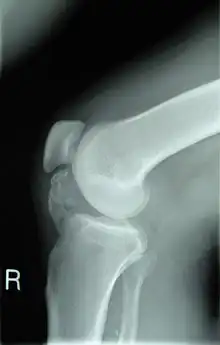

Lateral radiograph of the knee demonstrating ossification in the peritendinous tissues in a patient with osteochondroma. | |